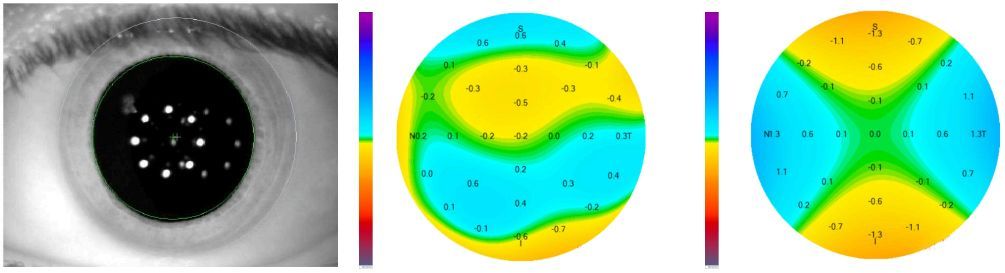

03角膜像差——全定制个性化数字验配

全角膜像差引导个性化验配。